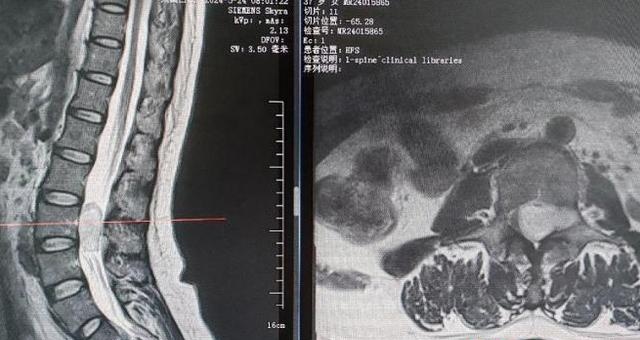

(▲术前腰椎增强磁共振)

该科副主任欧宣成接诊了王女士,经仔细询问病史、体格检查,结合胸腰椎MRI检查等诊断患者为“L3-4水平椎管内肿瘤”,考虑患者病情紧急,欧宣成建议她立即住院接受手术治疗。

王女士入院三天后,该科主任张勇、副主任欧宣成等脊柱外科一区团队联合神经外科、麻醉科、康复科等MDT团队为患者成功实施了全麻下的“腰椎管内肿瘤摘除+内固定融合术”,肿瘤摘除完全在显微镜下进行,手术顺利,历时3.5小时,患者肿瘤完整摘除,术中发现瘤体约4*2.5cm大小,术中出血不足100ml,术后病检显示肿瘤为神经纤维瘤。